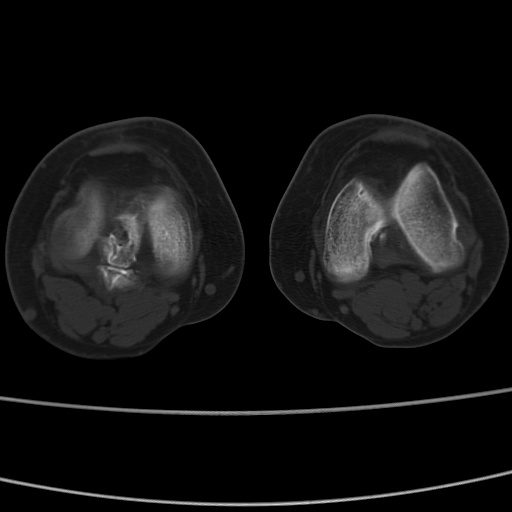

女性,50岁。【请提供患者临床症状体征】

右膝关节退行性改变,关节游离鼠。

右膝关节退行性改变,滑膜黏液囊钙/骨化并游离。

右膝关节退行性改变